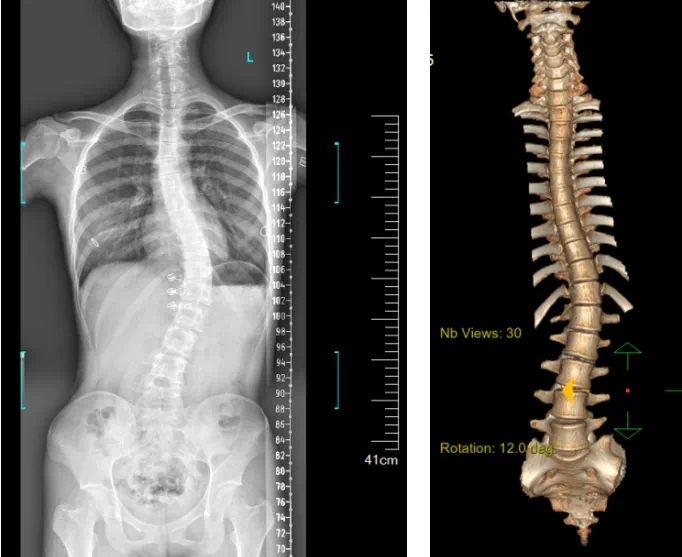

患者為一名16歲女孩,發(fā)現(xiàn)脊柱側(cè)彎1年,到南方醫(yī)院贛州醫(yī)院脊柱外科求診。經(jīng)查體,患者左右胸廓不對稱,雙肩等高,左肩胛骨隆起,背側(cè)呈“剃刀背”畸形,胸腰段棘突偏離正中線,胸腰段脊柱左側(cè)凸畸形;各棘突無壓痛及叩擊痛,右側(cè)腰部凹陷,胸腹及腰背部感覺正常。檢查發(fā)現(xiàn)患者特發(fā)性脊柱側(cè)彎,Lenke5C型,主胸彎51°?;颊呒凹覍賹ν庥^不滿意,為改善外觀及功能,要求手術(shù)矯形治療。

據(jù)悉脊柱側(cè)彎手術(shù)治療后可以保持軀干平衡,改善外觀并防止畸形進(jìn)一步發(fā)展?;颊叩纳钯|(zhì)量得到提高,進(jìn)而減少脊柱過度畸形可能帶來的疾病的發(fā)生率,外觀上的積極變化往往也能帶來患者心理與精神的積極變化。臨床上會綜合考慮患者的年齡、側(cè)彎程度、進(jìn)展趨勢、骨質(zhì)條件、鄰近節(jié)段情況、手術(shù)節(jié)段等因素,合理采用個性化的手術(shù)方式進(jìn)行治療。然而,由于脊柱神經(jīng)血管密布,手術(shù)操作相對復(fù)雜,手術(shù)難度高、風(fēng)險大,傳統(tǒng)脊柱側(cè)彎的手術(shù)方式往往有較高的神經(jīng)或脊髓損傷風(fēng)險。故此次科室決定開展機(jī)器人輔助導(dǎo)航下脊柱側(cè)彎矯形、植骨融合內(nèi)固定手術(shù)。術(shù)前,醫(yī)生團(tuán)隊在機(jī)器人多維度圖像融合智能手術(shù)規(guī)劃功能的輔助下,預(yù)先規(guī)劃了理想的置釘路徑。術(shù)中,天璣骨科手術(shù)機(jī)器人準(zhǔn)確遵循術(shù)前規(guī)劃,根據(jù)配準(zhǔn)結(jié)果,實時定位并準(zhǔn)確執(zhí)行置釘操作,所有導(dǎo)針均用電鉆置入,一次性成功,協(xié)助醫(yī)生順利完成手術(shù)。最終,在麻醉科、手術(shù)室密切配合下,歷時3小時成功完成側(cè)彎矯形術(shù),出血量僅500ml。術(shù)后,患者恢復(fù)良好,大小便及下肢神經(jīng)運動感覺正常。